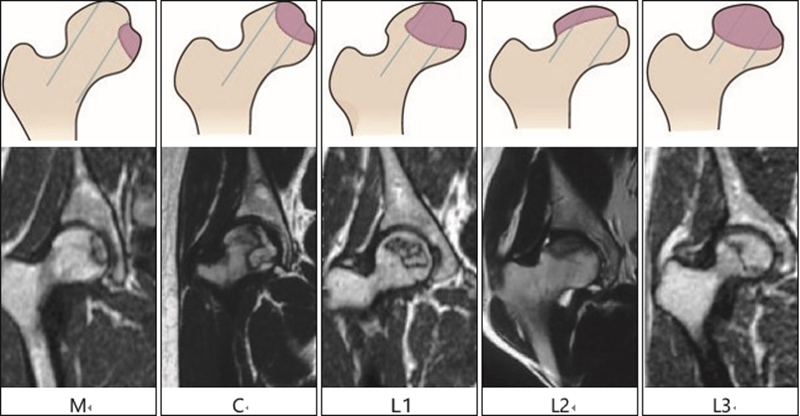

2014年12月,中华医学会骨科学分会关节外科学组组织国内骨坏死研究及诊疗专家讨论,制订了《股骨头坏死临床诊疗规范》[10],提出了中国分期;同时,推荐使用ONFH的CJFH分型[16]和中国分期。见图1,表2。CJFH分型按ONFH累及三柱结构的部位进行分型:M型(内侧型),坏死灶累及内侧柱;C型(中央型),坏死灶累及中央柱及内侧柱;L1型(次外侧型):坏死灶累及三柱,但外侧柱有部分存留;L2型(极外侧型),坏死灶累及外侧柱及部分中央柱;L3型(全股骨头型),坏死带穿透整个股骨头三柱皮质及骨髓。CJFH分型结果不会受解剖变异及位置移动的影响,且对ONFH塌陷预测的准确性高,对治疗方案的选择具有临床实际指导意义,应用简便、可重复性强。

图1 ONFH的CJFH分型示意图及MRI影像